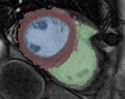

Most clinicians are using the EMSegmenter to segment specific parts of the human body. Those segmentations depend heavily on

the used input data. The signal level in the input data varies with the used image modalities (e.g. MRI, CT, ...) and with each anatomical structure.

The EMSegmenter can take advantage of some knowledge about the signal level of those anatomical structures in the different image modalities.

Technically, each tasks consist of a .mrml file and a .tcl file.

The .mrml file stores the anatomical properties (mean values, covariance values) in a user defined tree structure.

The .tcl script is used to perform some pre-processing on the input data.